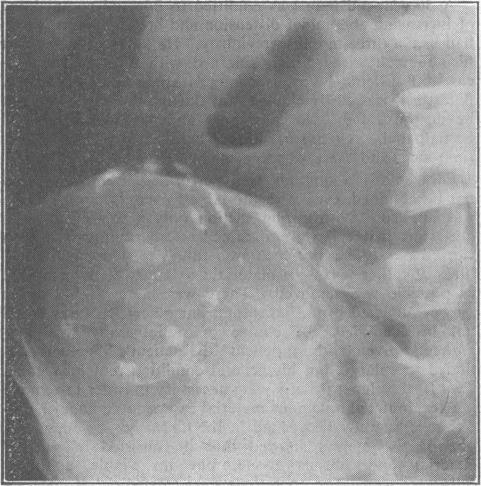

The diagnosis of pseudomyxoma peritonei.

Pseudomyxoma peritonei.

Two cases of pseudomyxoma peritonei from mucocele of the appendix.

[Pseudomyxoma peritonei].

Pseudomyxoma Peritonei in a Patient with History of Breast Cancer.